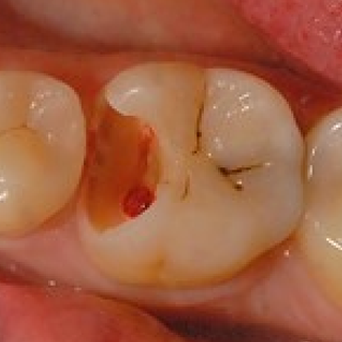

심한충치

충치가 신경까지 깊게 진행된 상태

주요 증상

- 지속적인 통증

- 씹을 때 아픔

- 잇몸 부종